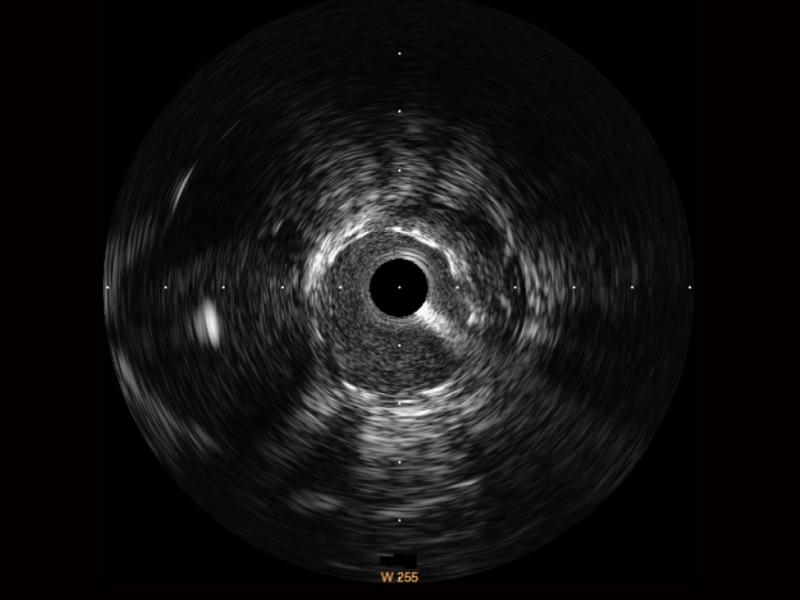

• 传统IVUS图像

对比传统IVUS导管成像,乐玩lewin国际宽频IVUS图像的近场支架梁显影更细腻,远场中膜外血管仍清晰可辨,兼顾远中近,兼顾分辨力与穿透深度